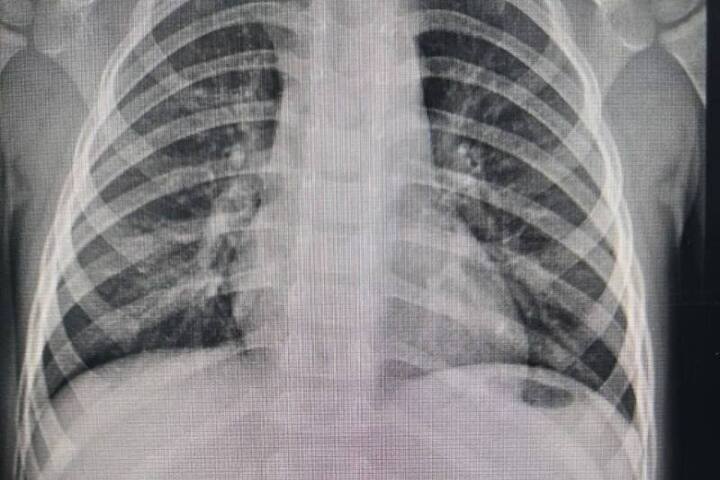

В Центр охраны материнства и детства доставили мальчика двух лет семи месяцев. У ребёнка наблюдалась высокая температура и сильные боли в животе. Врачи выяснили, что несколькими днями ранее малыш играл с магнитным конструктором и проглотил несколько деталей.

Ситуация оказалась критической: оказавшись в кишечнике, магниты начали притягиваться друг к другу через стенки органа. Это привело к сдавлению тканей и двойной перфорации кишечника — опасному состоянию, которое может вызвать тяжёлое воспаление и другие серьёзные осложнения.

Ребёнку немедленно провели хирургическую операцию. Врачи обнаружили в толстой кишке 19 магнитных элементов, успешно удалили их и ушили повреждённые участки кишечника.